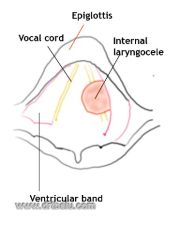

| 15:37, 22 October 2018 | Int cele.jpg (file) |  |

47 KB | Drtbalu | |